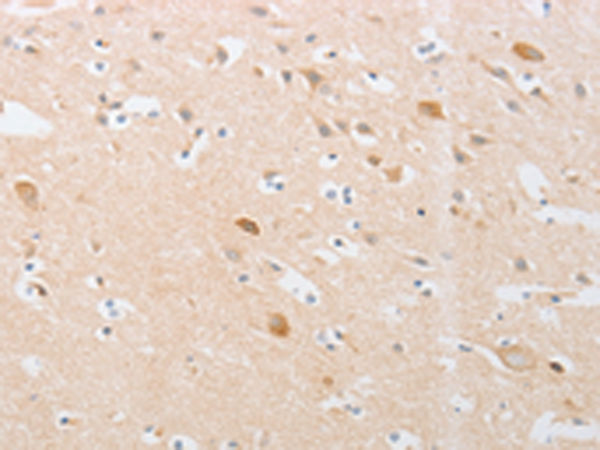

分类: 科研抗体货号: P07520别名: PAK65; PAKgamma应用: WB,IHC反应种属: Human, Mouse, Rat